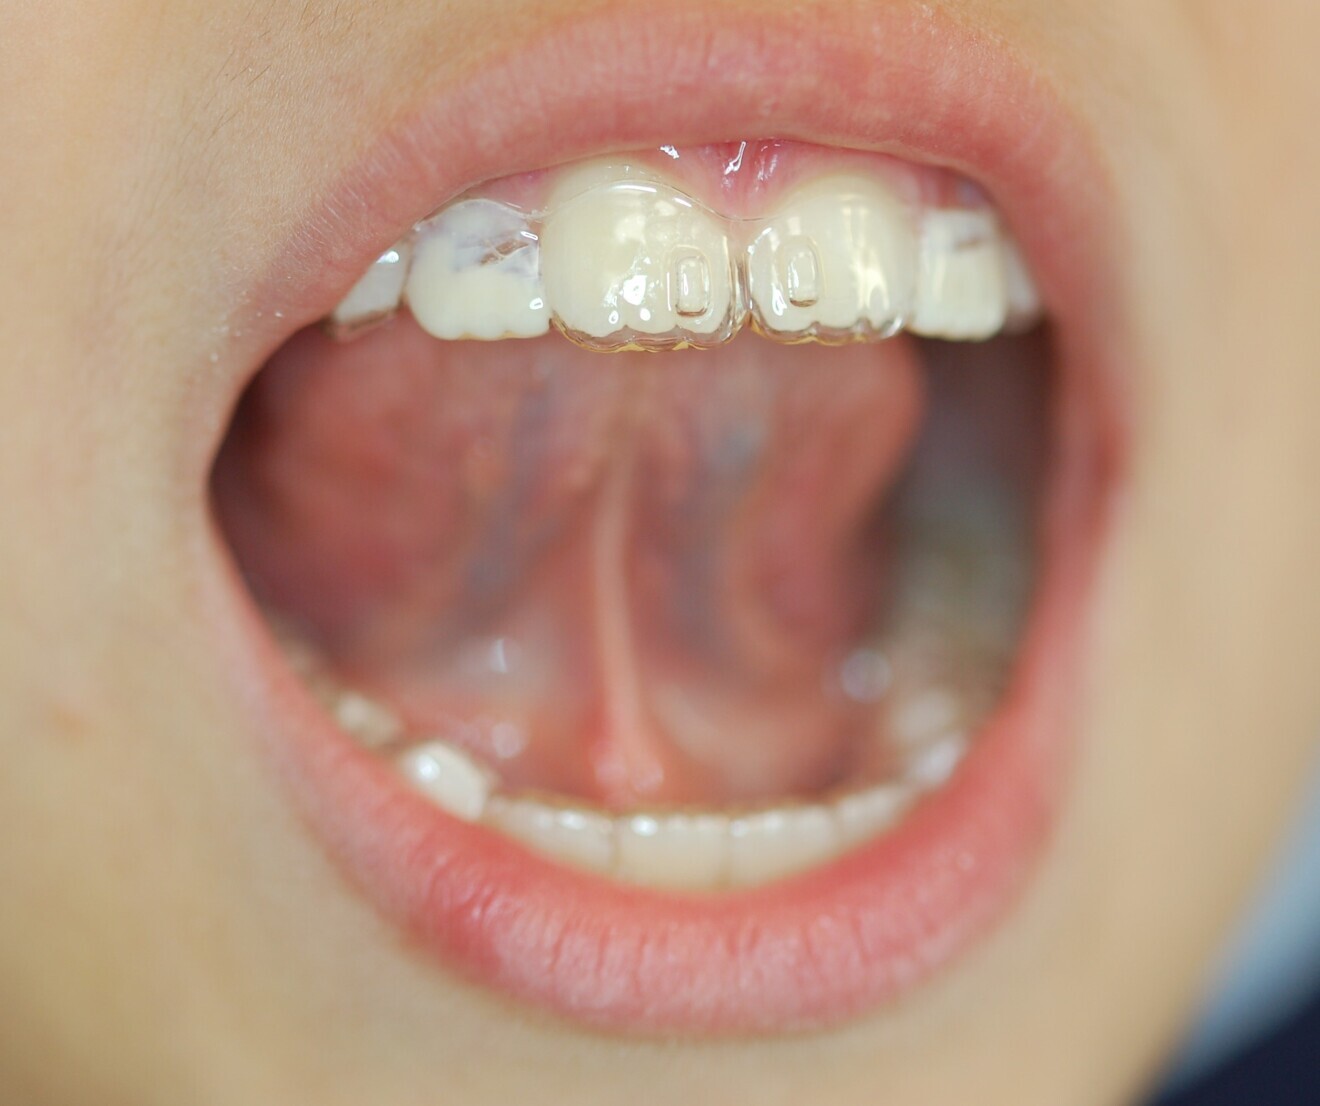

We decided to treat the patient with Nuvola Junior. Movement was to be achieved with 20 pairs of aligners initially, leaving eruption guides for teeth #12 and 22. The maxillary aligners used in the treatment have lingual pins (patented for the Nuvola OP system protocol) (Fig. 5) that prompt raising of the tongue tip towards the incisive papilla (Fig. 6). After the planned 20 pairs of aligners, eight finishing pairs were made especially to align teeth #12 and 22. The aligners were worn all night and for 2 hours during the day and changed every 14 days.

For 30 minutes per day, the patient was required to wear the Intercept myofunctional device24–27 along with the aligners. In addition to the features common to the most popular trainers (lingual ramp, vestibular shields and occlusal support plane), the device has innovative horizontal proprioception lines (Fig. 7), two on the lower flange and two on the upper. This device is used to train the patient on correct lip posture; normally, altered lingual posture also corresponds to altered lip posture and strength.